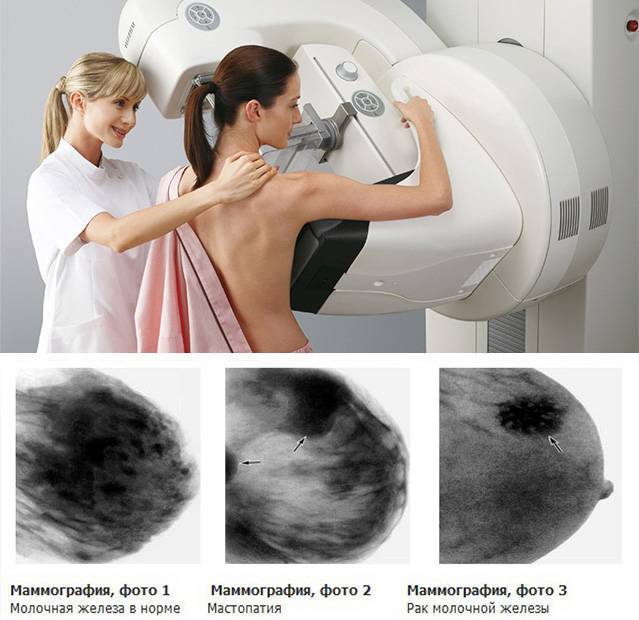

Феномен гипердиагностики в маммографии: примеры и иллюстрации

Раздел: Образы вокруг